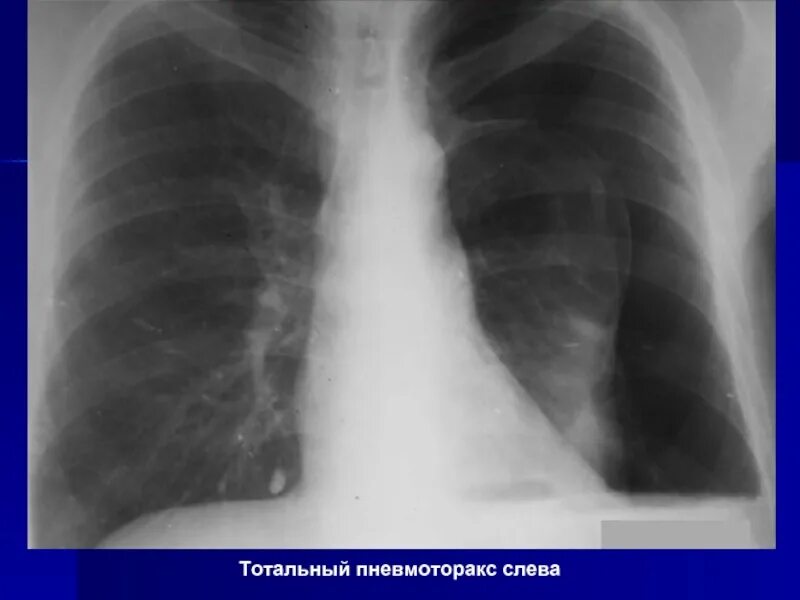

Коллабированное легкое при пневмотораксе